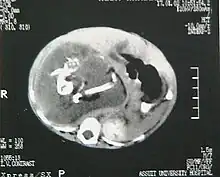

Fetus in fetu

There are two hypotheses for the origin of a "fetus in fetu". One hypothesis is that the mass begins as a normal fetus but becomes enveloped inside its twin.[2] The other hypothesis is that the mass is a highly developed teratoma. "Fetus in fetu" is estimated to occur in 1 in 500,000 live births.[3]

A fetus in fetu can be considered alive, but only in the sense that its component tissues have not yet died or been eliminated. Thus, the life of a fetus in fetu is akin to that of a tumor in that its cells remain viable by way of normal metabolic activity. However, without the gestational conditions in utero with the amnion and placenta, a fetus in fetu can develop into, at best, an especially well differentiated teratoma; or, at worst, a high-grade metastatic teratocarcinoma. In terms of physical maturation, its organs have a working blood supply from the host, but all cases of fetus in fetu present critical defects, such as no functional brain, heart, lungs, gastrointestinal tract, or urinary tract. Accordingly, while a fetus in fetu can share select morphological features with a normal fetus, it has no prospect of any life outside of the host twin. Moreover, it poses clear threats to the life of the host twin on whom its own life depends.[4]